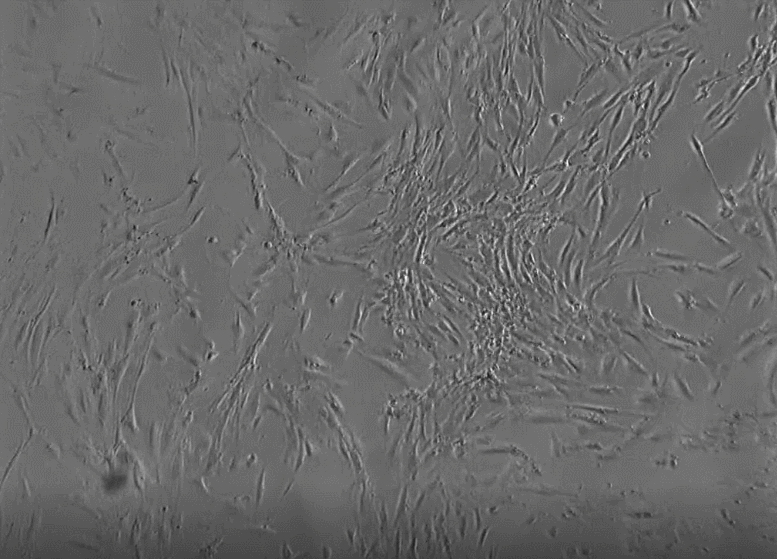

干细胞近些年来慢慢走进了大家的视野当中,经常有人会提出自己的疑问:静脉输注干细胞真的安全吗?今天我们就分享给大家

总结了2012年至2019年的间充质干细胞临床随机试验,结果一如既往的证实了间充质干细胞的安全性。